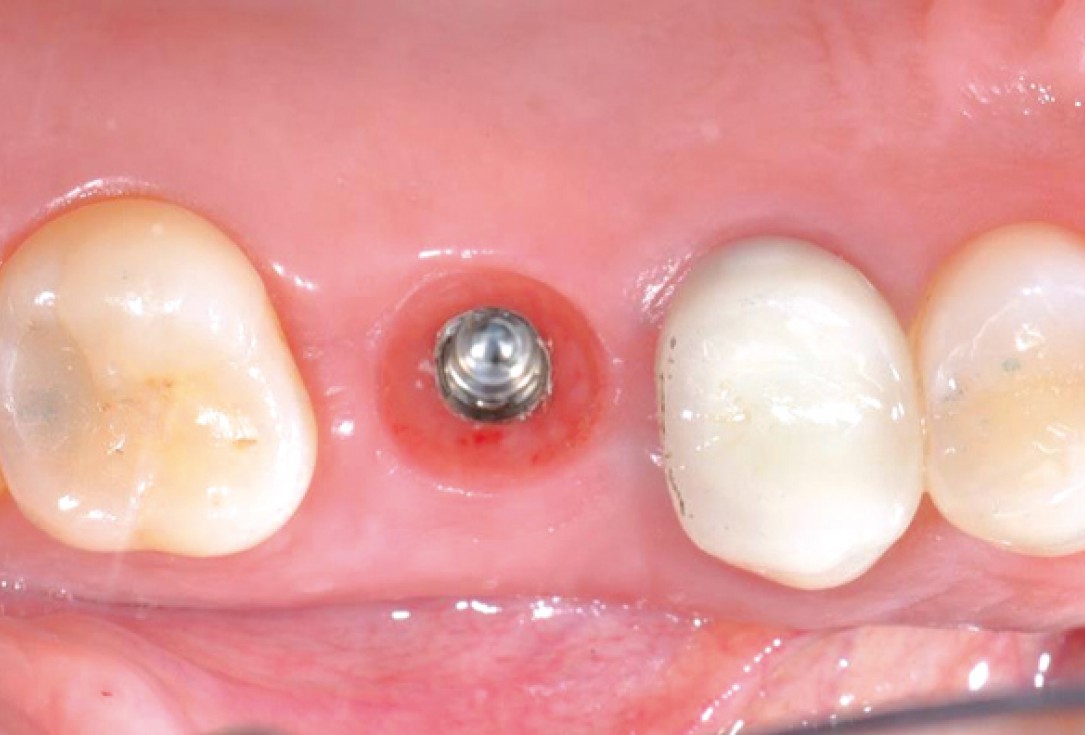

7/11 - Osseointegration and soft tissue healing after 45 daysSealing of a postextraction socket with mucoderm® - Dr. M. Frosecchi